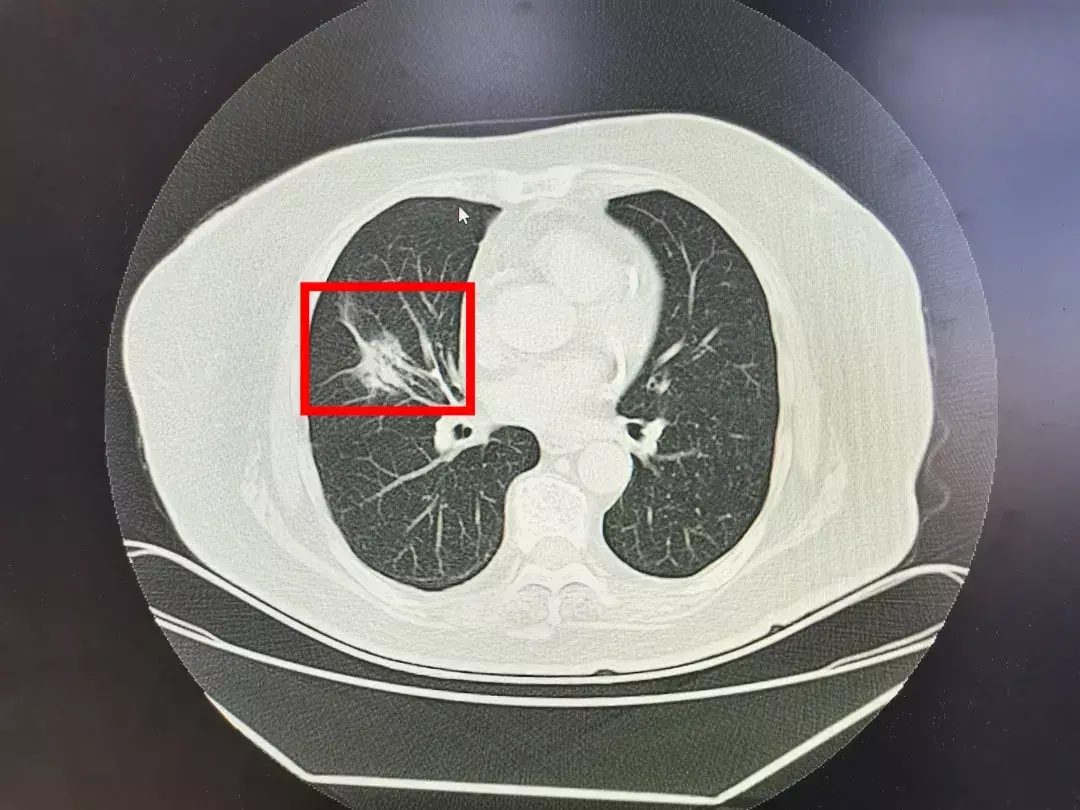

他儿子广先生觉得事情可能没那么简单,带着老太太来到西安市人民医院·西安市第四医院新院区胸部疾病治疗中心杨锋主任的门诊。杨主任详细的询问了老太太的病史,并复查了一下胸部CT胸部CT上这个阴影有3.5*2cmCT,检查结果:红色方框为阴影部分,确实不是打个“消炎针”就能消除的。考虑是肺癌。